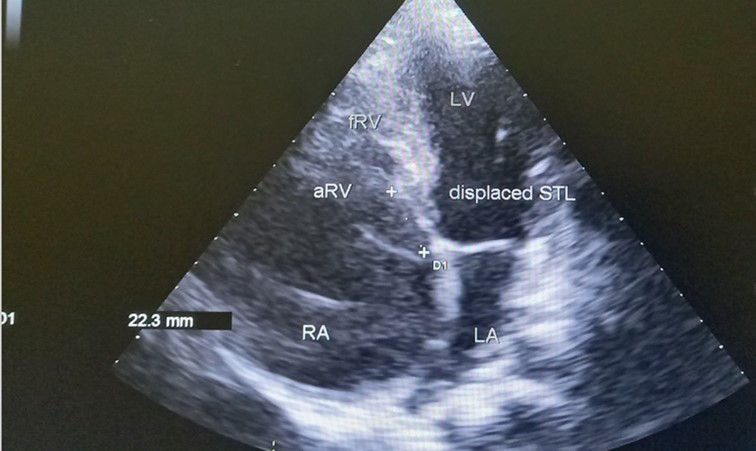

The patient underwent echocardiography (Figure 3 ) showing a low insertion of the septal and posterior leaflets of the tricuspid valve 22 mm below the tricuspid annulus, the anterior leaflet having reduced reduced mobility. Significant dilatation of the the right atrium by atrialisation of the right ventricle (RV). The rudimentary RV and its atrial stump are dilated and responsible for compression of the LV. There was no tricuspid insufficiency. No other associated congenital anomaly. However, we found a large floating thrombus in the right atrium measuring 64 mm x 30 mm in diameter. This was therefore Ebstein's disease at stage C of the Carpentier classification. The apical displacement of the tricuspid septal valve was 22 mm or 15 mm/m2). The surface area of the atrium and the atrialized right ventricle was 45 cm2 , the surface area of the right ventricle and the left cavities was 30 cm2 , the Celermajer index was calculated at 1.4 ( Grade 3).

Figure 3.Transthoracic echocardiography, apical four chambers view . Apical displacement of the tricuspid valve (a) and right atrial thrombus (b).

Echocardiography is an essential diagnostic test and allows accurate assessment of the tricuspid valve leaflets and the size and function of the heart chambers. The main feature of Ebstein’s anomaly is an apical displacement of the tricuspid septal leaflet of at least 8 mm/m2. The average displacement in our patient was 15 mm/m2

In 1988, Carpentier et al proposed the following classification of Ebstein’s anomaly: type A, the volume of the true right ventricle is adequate; type B, a large atrialized component of the right ventricle exists, but the anterior leaflet of the tricuspid valve moves freely; type C, the anterior leaflet is severely restricted in its movement and may cause significant obstruction of the right ventricular outflow tract; and type D, almost complete atrialization of the ventricle except for a small infundibular component 8, 11.

Celermajer et al described an echocardiographic grading score for neonates with Ebstein’s anomaly, extended Glasgow Outcome Scale, with grades 1 to 4. The ratio of the combined area of the right atrium and atrialized right ventricle is compared with that of the functional right ventricle and left heart (ratio <0.5, grade 1; ratio of 0.5 to 0.99, grade 2; ratio of 1.0 to 1.49, grade 3; ratio ≥1.5, grade 4) 8, 11.

In our case, the patient had, type C of EA and Grade 2. The investigation also revealed a large thrombus floating in the right atrium and no obvious regurgitation of the tricuspid valve. In addition, the septa was intact, there was no persistence of the ductus arteriosus, the pulmonary and aortic pathway were unobstructed.